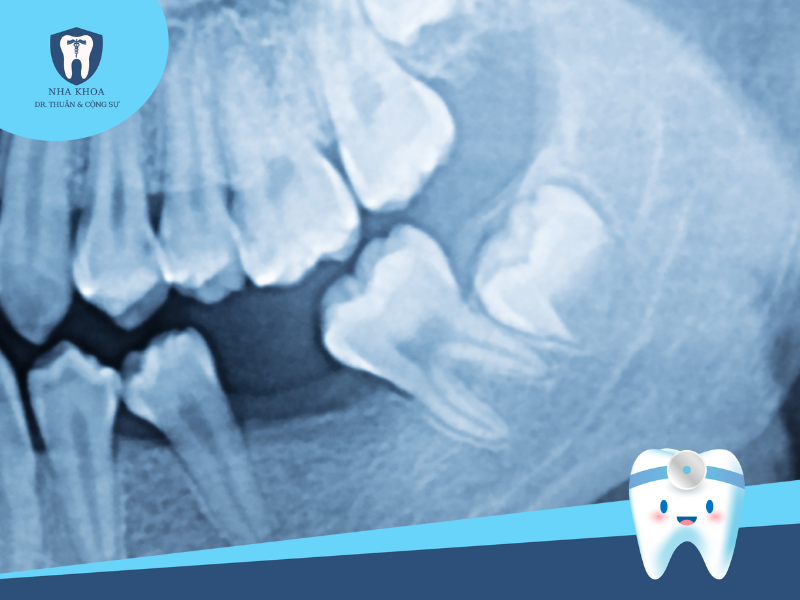

Bước 1: Khám tổng quát và chụp phim X-quang

Đây là bước đầu tiên nhưng cũng rất quan trọng trong quy trình nhổ răng khôn. Theo đó, nha sĩ sẽ thực hiện các biện pháp thăm khám để đánh giá tình trạng tổng quát, cũng như khám kĩ để xem xét tình trạng, vị trí, mức độ tổn thương... của răng. Sau đó, bác sĩ sẽ cho bệnh nhân chụp phim X-quang hàm răng để đánh giá hình ảnh chính xác về tư thế và vị trí răng khôn mọc, giúp nha sĩ nắm rõ và xây dựng kế hoạch nhổ răng phù hợp và ít sang chấn cho người bệnh.

Răng khôn mọc lệch khi nhìn qua X-quang